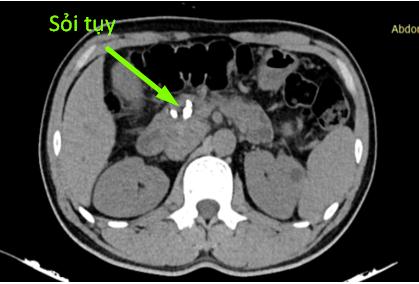

Trường hợp thứ nhất: bệnh nhân nam N.V.B 50 tuổi, có thói quen uống rượu từ năm 20 tuổi, mỗi ngày trung bình 150ml. Đợt này anh B thấy đau bụng âm ỉ quanh rốn, thượng vị, ở nhà tự mua thuốc giảm đau không đỡ. Một tháng gần đây, anh đau bụng tăng lên kèm ăn uống kém. Qua bạn bè giới thiệu, anh B đến khám tại phòng khám của Khoa Phẫu thuật tiêu hóa – Gan mật tụy. Phim chụp cắt lớp vi tính cho thấy hình ảnh nhu mô tụy teo nhỏ, ống tụy giãn 1 cm và trong có rất nhiều sỏi. Người bệnh được chẩn đoán sỏi tụy/viêm tụy mạn – nghiện rượu và được phẫu thuật theo phương pháp Frey (mở dọc ống tụy từ đầu đến đuôi tụy, lấy tổ chức đầu tụy sinh thiết, nối tụy ruột). Sau mổ, bệnh nhân được sử dụng hệ thống giảm đau, kết hợp vận động sớm sau mổ và can thiệp dinh dưỡng. Bệnh nhân B được ra viện sau 7 ngày phẫu thuật. Hiện tại, tình trạng bệnh nhân ổn định, hết đau bụng, ăn uống sinh hoạt bình thường, đã bỏ rượu theo tư vấn của bác sĩ.

Hình 1: Ảnh trên cắt lớp vi tính và trong mổ của bệnh nhân B

(mũi tên chỉ sỏi tụy)